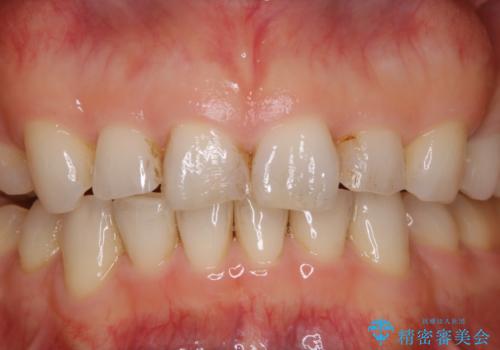

一か所茶色く色が残っている所がありますが、これは詰め物の変色です。

以前にCR(コンポジットレジン)による虫歯の治療での充填がされています。

CRは経年的に劣化や変色、着色がついてしまいます。

PMTCでしっかりとクリーニングを行うと、古いCRが目立つことがあり、気になる際は詰め替えを行います。